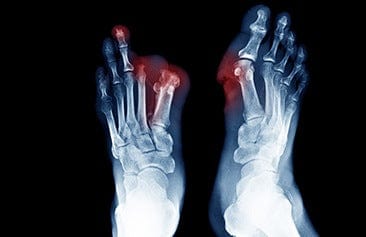

Bone infections are difficult to identify because they frequently resemble other forms of diseases or injuries. Your doctor will most likely begin with a physical examination and questions about your medical history. They may also request tests like X-rays, MRIs, or blood tests. Antibiotics and surgery are frequently used to treat a bone infection. In order to better understand Bone Infection, Welzo users should read this article.